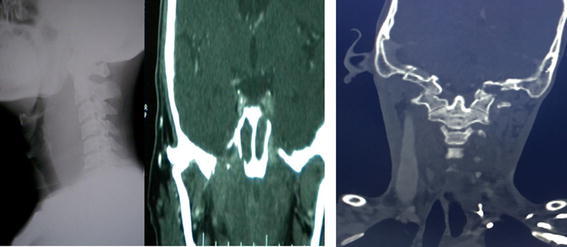

Fig. 2.

(Case 3 and 7) X ray soft tissue neck (lateral view) showing smooth bulge of prevertebral tissue and CECT revealed heterogenous mass in spheno-petero-clival region with erosion of surrounding bones